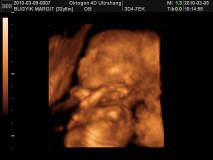

Megvolt az Uh és doktornő uh-on megint rendben talált mindent. Olyan kis édes volt. Kivételesen aludt, felébredt, elaludt. Nem volt akkora ugra-bugra most.

Kitaláljátok a nemét? :lol: